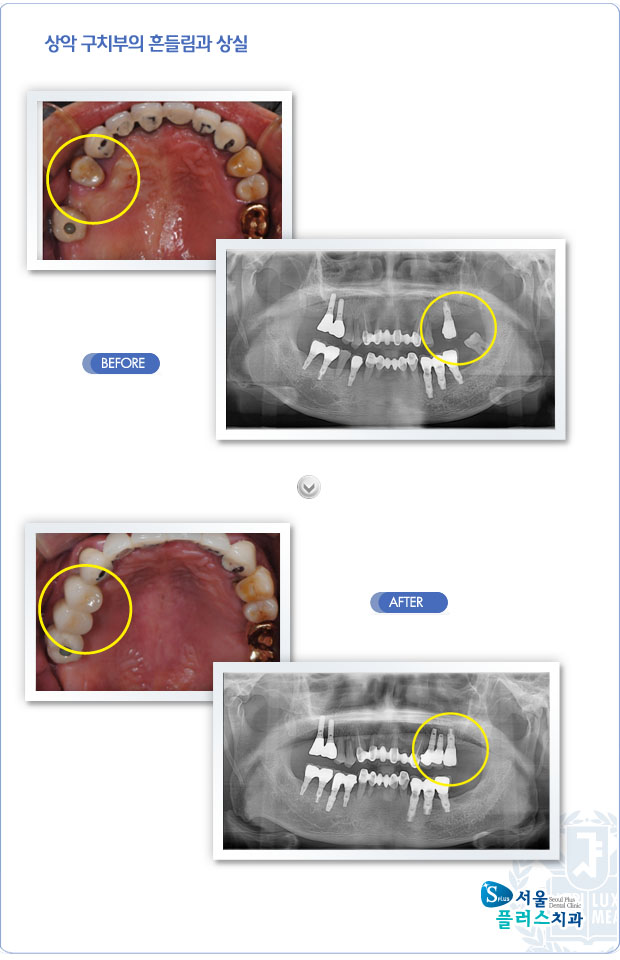

[임플란트] 상악 구치부의 흔들림과 상실